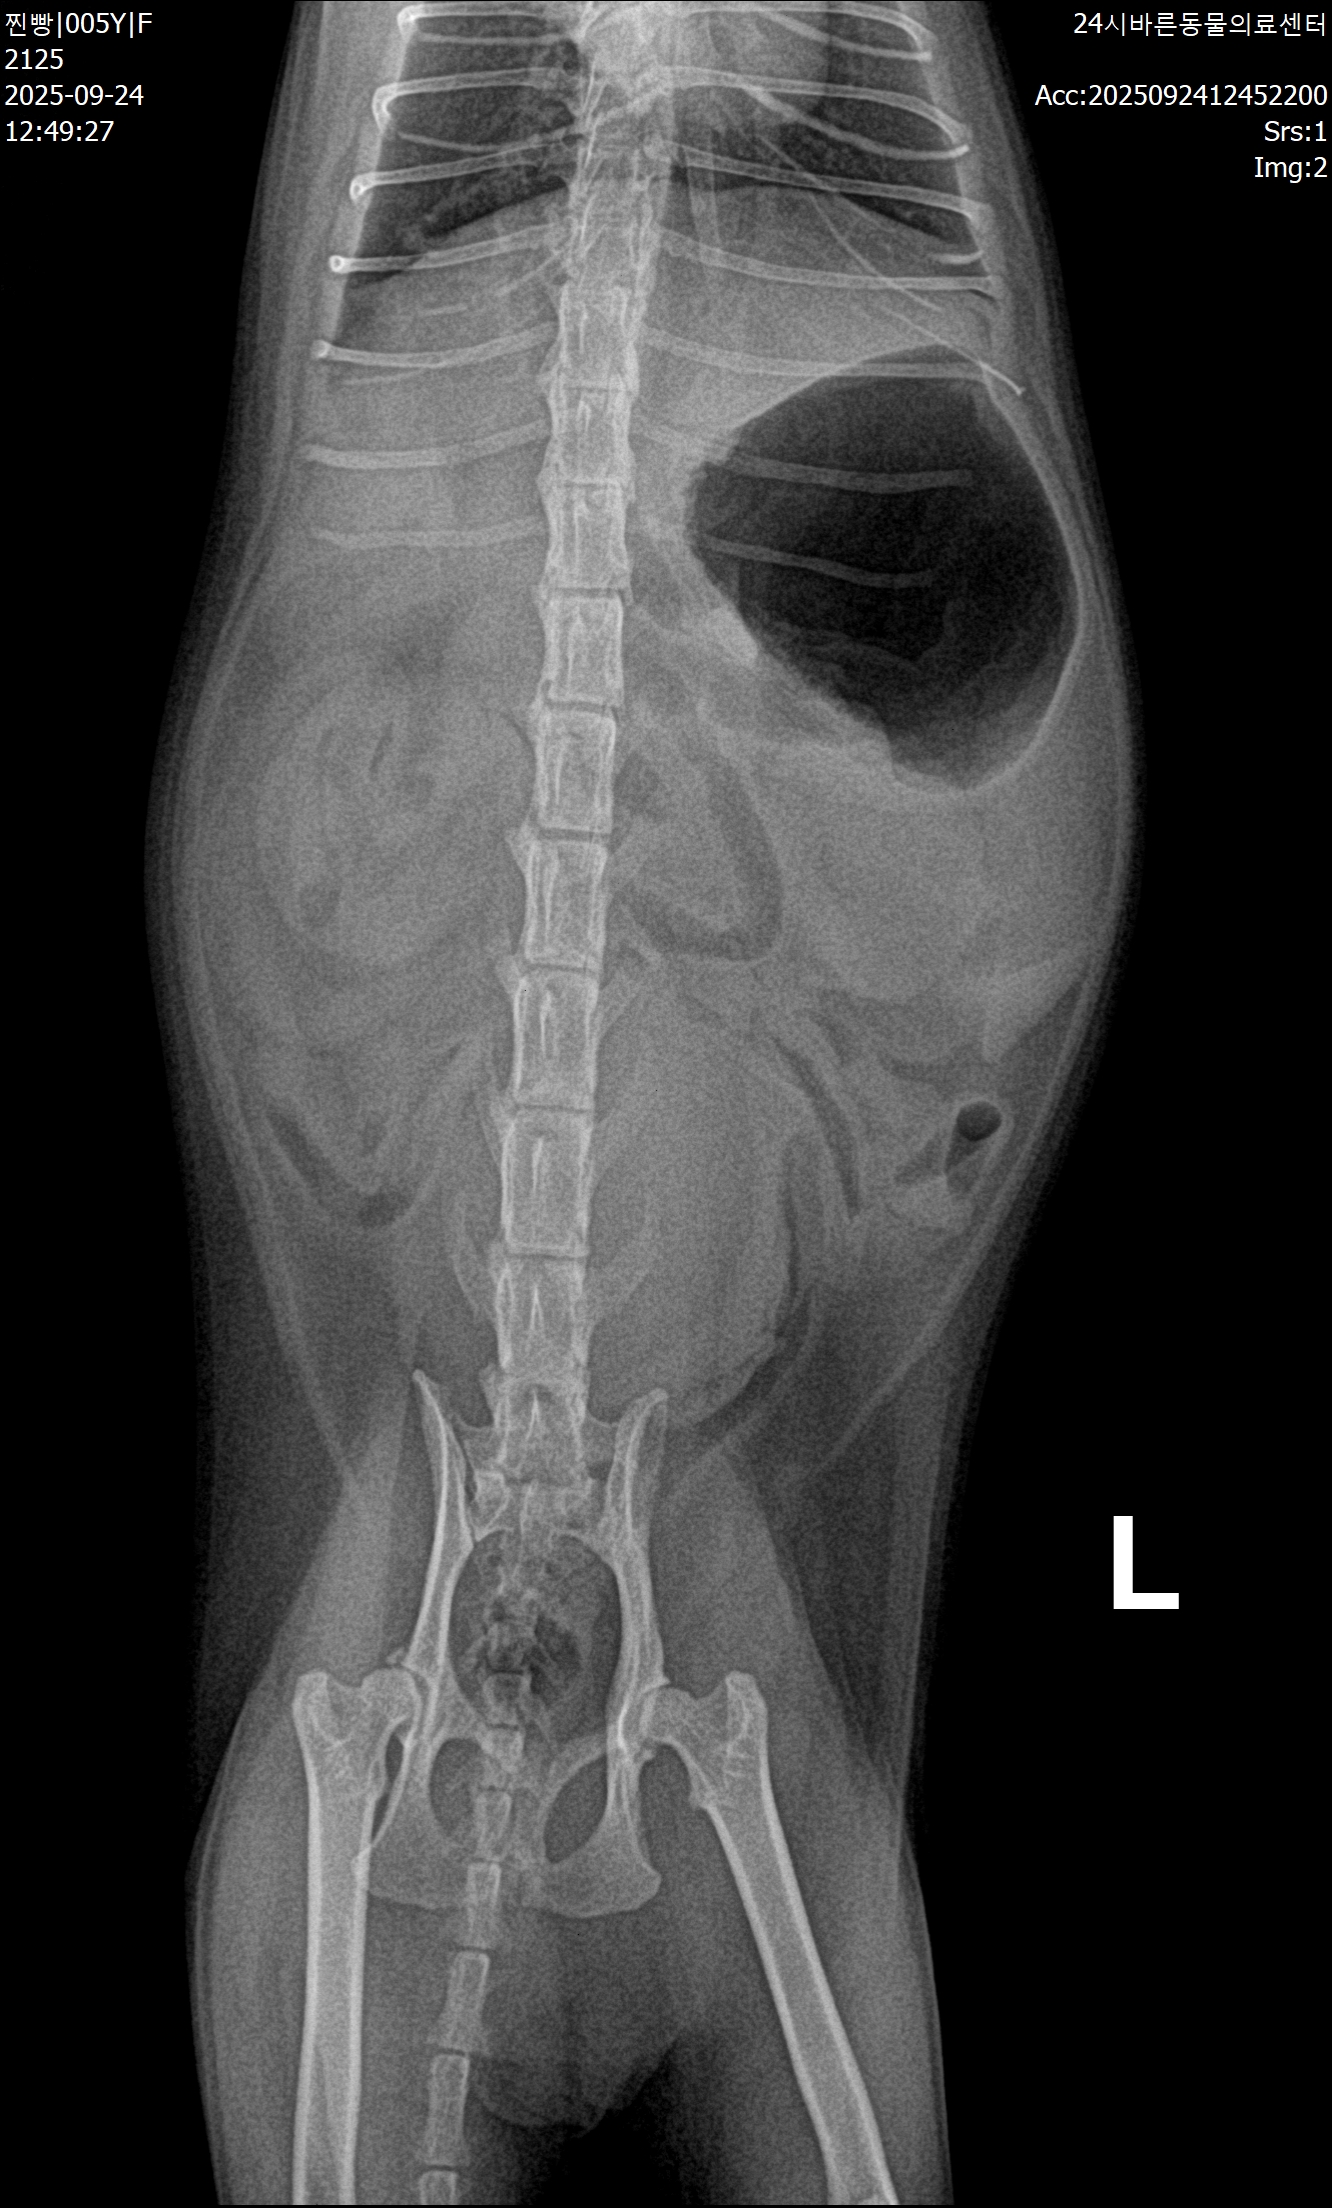

| 이전 | 찐빵이 고양이복막염32일차 경험담 | 찐빵이네 | 2025-11-12 |